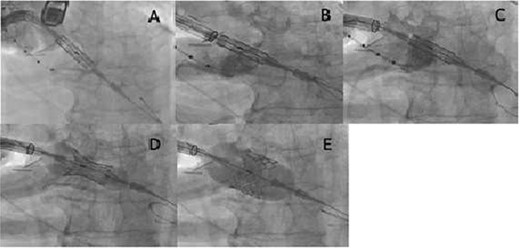

A male octogenarian patient with symptomatic severe aortic valve stenosis underwent TAo-TAVI because he had highly stenotic common iliac arteries. A right third intercostal surgical incision was made and an 18-Fr introducer sheath was placed at the middle of the ascending aorta. The Certitude delivery system with a 26-mm Sapien S3 transcatheter aortic valve (Edwards Lifesciences, Irvine, CA) was advanced over an extra-small Safari wire (Boston Scientific, Marlborough, MA). However, the Sapien S3 was not able to pass through the aortic valve owing to severe aortic valve stenosis (Fig. 1A). Multiple attempts to pass the valve prosthesis did not work. Because the valve prosthesis was already released from the loader, it could not be brought back into the Certitude system. In this situation, we considered two options: (i) to remove the Sapien S3 together with the Certitude system and restart TAo-TAVI using another system, or (ii) to insert another sheath into the ascending aorta to perform BAV. However, the first option would have been expensive, and the second seemed to be dangerous because the working space through the mini-thoracotomy was very limited.

(A) The Sapien S3 did not pass into the aortic valve, and the Certitude system bounced back toward reverse direction; (B) the Sapien S3 was forcefully pushed together with the Certitude system, and the Sapien S3 finally came into the aortic valve; (C) the Certitude system was pulled back to enable dilatation; (D) the Sapien S3 was slowly deployed to avoid malposition; (E) the Sapien S3 was completely deployed

We then decided on a third option of pushing the Sapien S3 forcefully together with the Certitude system (Fig. 1B). With careful pulling, enough countertraction was given to the Safari wire to ensure the direct transmission of power to the Sapien S3 while simultaneously avoiding injury to the left ventricle by the Safari wire. The Sapien S3 was successfully brought into the aortic valve. Thereafter, the Certitude system was pulled back to near the aortic wall (Fig. 1C), and the Sapien S3 could be deployed as usual (Fig. 1D and E). The postoperative course was uneventful and the patient was discharged home on the 10th postoperative day.